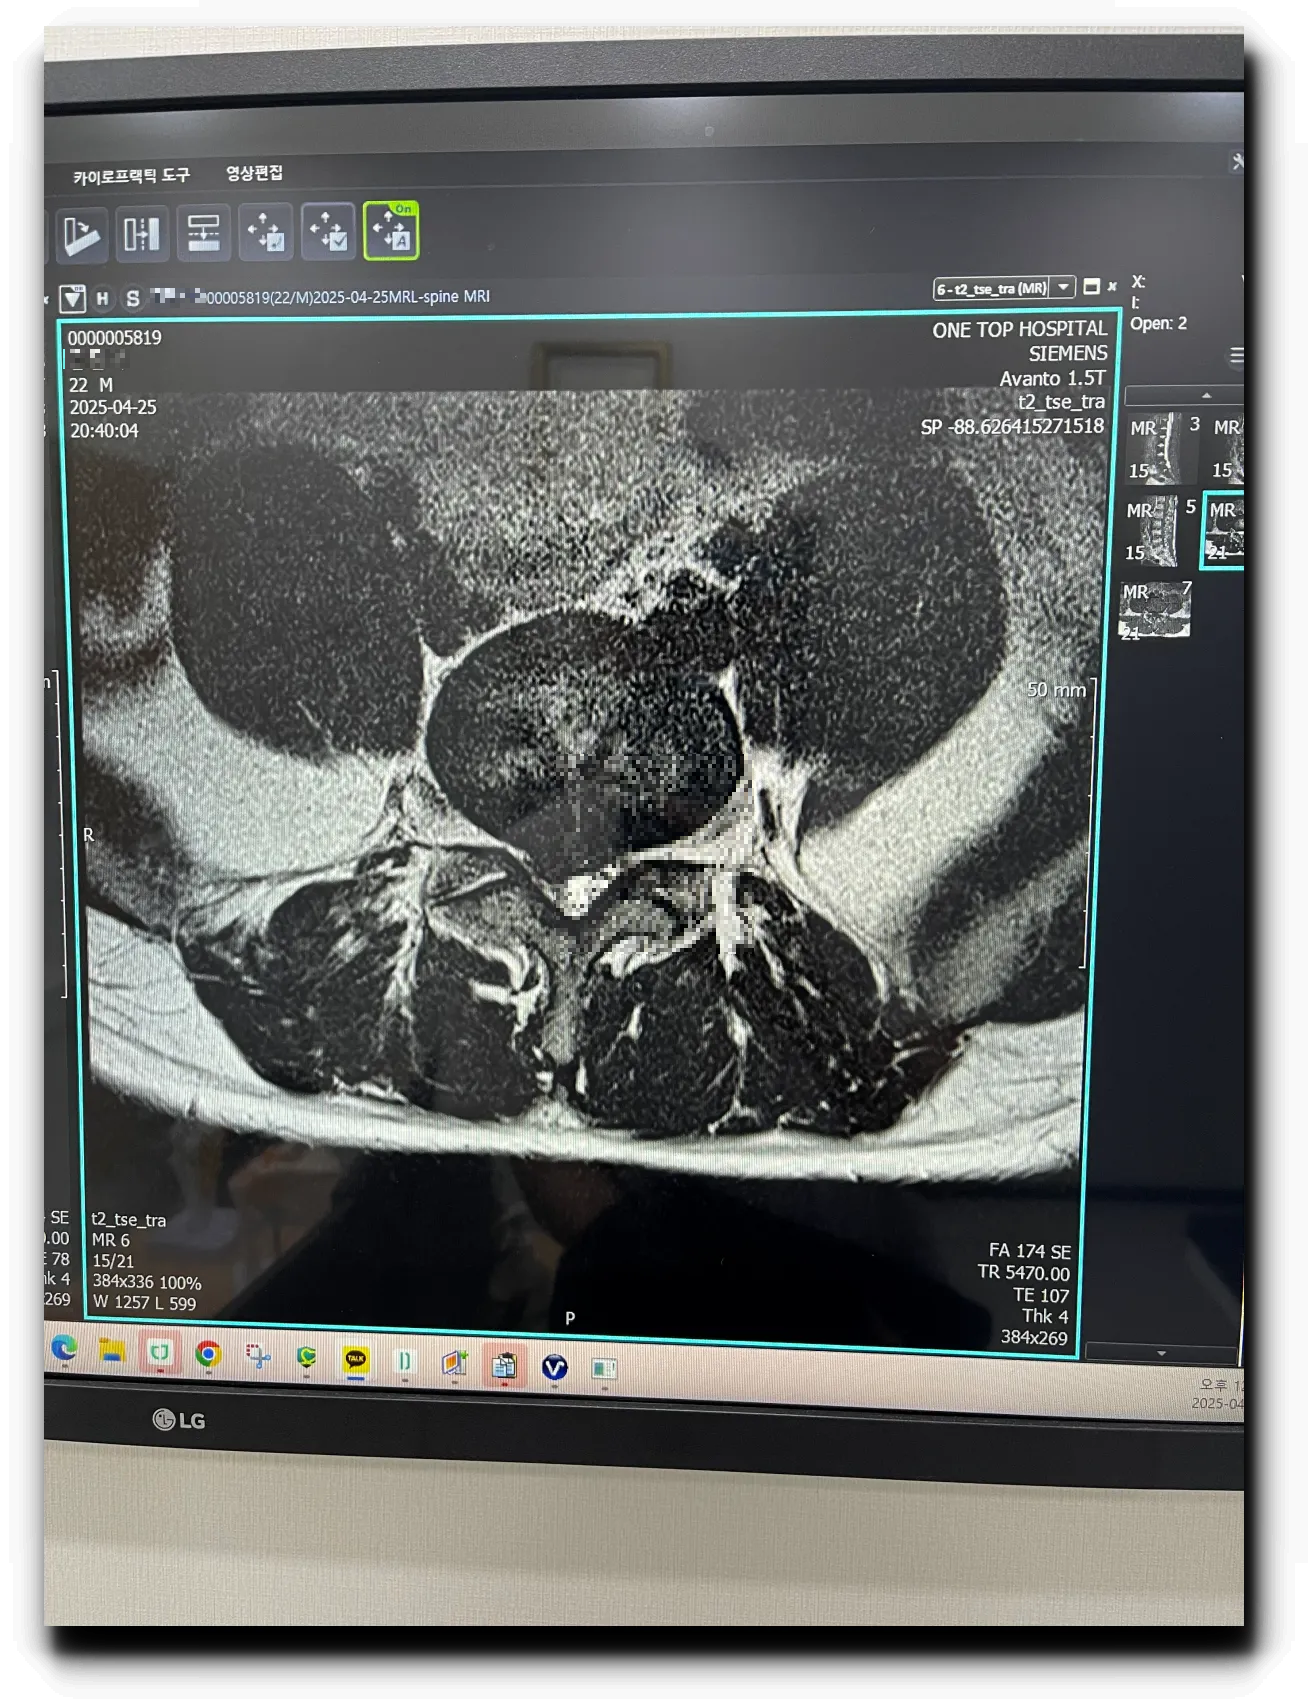

- 요추 4-5 사이가 많이 탈출해서 신경을 50% 이상 누르고 있다

- 요추 4-5 사이의 심한 탈출로 오른쪽 다리 방사통을 유발한다